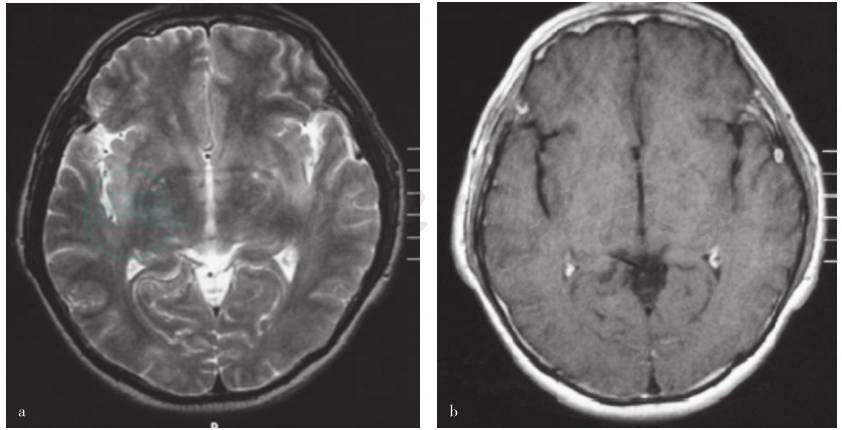

图2 患者头部MRI检查

横断面T2WI显示双侧额叶皮质及皮质下、侧脑室

血常规检查白细胞计数为11.82×109/L,中性粒细胞比例0.75,血红蛋白129g/L,血小板计数400×109/L;红细胞沉降率41mm/h,C反应蛋白47mg/L;血清乳酸、梅毒快速血浆反应素试验(RPR)、EB病毒抗体和结核菌素纯蛋白衍生物皮肤试验均呈阴性。甲状腺功能、肿瘤标志物 CA 系列[包括CA199,CA50,CA242,甲胎蛋白(AFP),癌胚抗原(CEA)等]和肺癌标志物筛查基本于正常值范围。血清抗脑组织抗体(抗Hu、Yo、Ri抗体)呈阴性反应;抗中性粒细胞胞质抗体(ANCA)、抗核抗体、抗双链DNA抗体(dsDNA)、抗可提取性核抗原抗体、类风湿因子(RF)、抗心磷脂抗体(ACA),以及补体C3、C4、免疫球蛋白及血清免疫电泳检测均正常;淋巴细胞表型分析CD4/CD8细胞比例未见异常;人类白细胞抗原B27(HLA-B27)呈阴性反应。腰椎穿刺脑脊液检查压力为170mmH2O,脑脊液常规:白细胞计数8×106/L,蛋白0.75g/L,葡萄糖3.90mmol/L,氯化物117mmol/L;脑脊液细胞学结果:淋巴细胞比例95%,符合以淋巴细胞主的炎性反应;24小时免疫球蛋白合成率正常,未见寡克隆区带(OCB),髓鞘碱性蛋白(MBP)10.98nmol/L。心电图、心脏超声、经颅多普勒超声(TCD)、双侧颈动脉和椎动脉彩色超声均未见明显异常。肺CT平扫及增强扫描未发现明显异常影像。头部MRI检查,弥散加权成像(DWI)和增强扫描均显示双侧额叶皮质及皮质下、双侧基底节区、双侧侧脑室旁、内侧颞叶斑片状长T2异常信号(图2),较外院影像无明显改变。核素扫描全身骨显像无异常。脑电图报告呈边缘状态。简易智能状态检查量表(MMSE)评分为17分(异常)。耳鼻咽喉科会诊:双侧轻度传导性听力下降,考虑双侧分泌性中耳炎。与患者及家属沟通后行耳郭组织活检。

该患者为中年男性,急性发病,亚急性病程,病情呈波动性变化,发病初期主要表现为系统性疾病症状,曾在其他医院先后被诊断为“反应性关节炎”“巩膜炎”和“右耳郭软骨膜炎”等,就诊期间还出现皮肤损害。近4个月来反复发热及神经系统症状,如头痛、发热、记忆力减退和精神行为异常等症状。病程中及入院后实验室检查白细胞计数、红细胞沉降率及血清C反应蛋白水平等炎性指标均显著升高;多次脑脊液检查提示白细胞计数、蛋白定量轻度升高,符合淋巴细胞炎性反应。头部MRI扫描显示双侧额叶皮质下、双侧基底节区、双侧侧脑室旁、内侧颞叶斑片状长T2异常信号。定位诊断:可将患者记忆力减退、精神行为异常和高级智能活动下降(定向力、记忆力、计算力等)等症状定位于双侧额颞叶;而四肢肌张力增高、不自主运动则定位在双侧基底节锥体外系。结合影像学检查病灶所在脑区,可以解释患者目前的临床症状及体征。另外,对于全身多系统损害表现,包括皮肤陈旧性色素沉着、眼结膜溃疡、耳郭发红等,考虑全身系统性受累。定性诊断:首先应考虑中枢神经系统炎症性疾病,包括感染性及非感染性炎症。根据患者亚急性病程,临床表现为发热、头痛、记忆力减退、精神行为异常等,首先,应排除病毒性脑炎的可能。但患者病程较长,约6个月,且病情反复波动,经抗病毒治疗病情仍有反复并呈渐进性加重,说明抗病毒治疗效果欠佳,此亦不符合病毒感染自限性之特点。其次,该患者影像学呈现颅内广泛性病灶,对于灰、白质并无太多的选择性,与单纯疱疹病毒性脑炎的典型灰质受累、额颞叶为主的出血坏死影像学图像不相符;同时入院后脑电图检查亦未发现典型的颞叶或以颞叶为中心累及额叶的周期性放电,因此均不支持病毒性脑炎的典型表现。对于非感染性炎性疾病方面,应注意与中枢神经系统炎性脱髓鞘性疾病急性播散性脑脊髓炎(ADEM)相鉴别。由于该患者的病程及影像学表现与急性播散性脑脊髓炎的急性发病、单相病程、白质受累为主和发病前多有感染或疫苗接种史不符,故以上两种疾病均不支持。目前,患者有多系统及脏器受累的临床表现,且先于神经系统症状出现,支持其原发病为全身系统性疾病而神经系统损害仅为其相应表现的诊断。鉴于患者在整个病程中先后出现眼、耳、关节等多器官或系统受损,并以软骨炎为特异性表现同时伴发中枢神经系统损害,故应首先考虑复发性多软骨炎伴中枢神经系统炎性病变;建议进行耳郭病理活检证实。